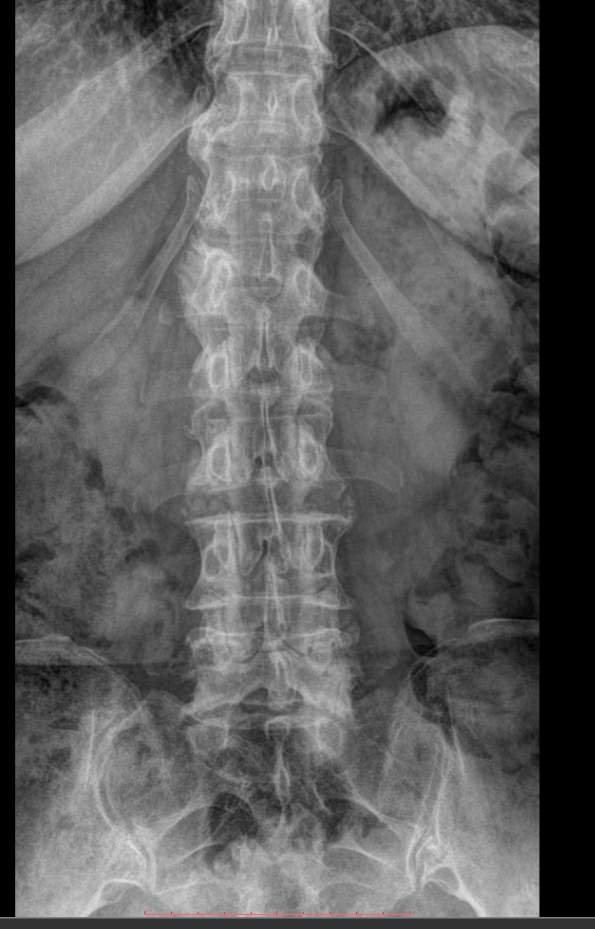

Поясничные позвонки, с 1 по 5, самые крупные во всем позвоночнике, так как удерживают большой груз ― всю верхнюю половину тела. Это последние отдельные позвонки, следующие 5 крестцовых позвонков срастаются в единую крестцовую кость. Благодаря массивности поясничный отдел может выдержать довольно сильные удары, однако травмы наблюдаются и в этом месте. Но большая часть патологий поясницы вызвана хроническими дегенеративно-дистрофическими изменениями. И чаще всего они развиваются в пояснично-крестцовом сочленении.Увидеть произошедшие с позвоночником изменения позволяет рентгенография. На снимке обычно видны все 5 поясничных, 12-й грудной и 1-й крестцовый позвонки. В некоторых случаях врачу необходим обзор крестца до уровня 3-4 позвонков. Снимки выполняются всегда в 2 проекциях.

Что покажет рентген поясничного-крестцового отдела позвоночника

• Сохранение или изменение поясничного лордоза;

• Признаки сколиоза: искривление оси позвоночника, в какую сторону, на сколько градусов, на уровне какого позвонка, с ротацией или без;

• Признаки нестабильности в поясничном отделе позвоночника

• Изменение высоты тел позвонков и межпозвонковых дисков ;

• Дистрофические изменения тел позвонков, костные разрастания, склероз;

• Наличие грыж Шморля;

• Травматические повреждения;

• Новообразования.